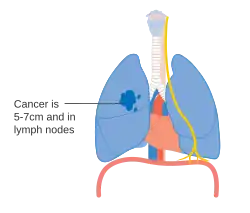

Stage IIA lung cancer

Stage IIA lung cancer -